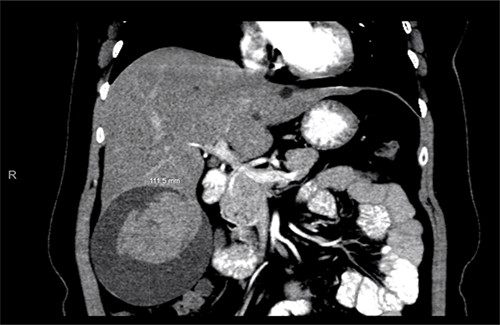

A computed tomography (CT) scan with intravenous (IV) contrast of the abdomen (Fig. 1) was performed and demonstrated a large 12 × 11 × 10 cm round exophytic complex hepatic cyst containing central soft tissue density mass and septations with multiple small hepatic cysts throughout liver. A hemorrhagic component within the cyst was also seen. In order to further delineate the cyst’s relationship to the biliary tree and surrounding structures, magnetic resonance imaging (Fig. 2) was also performed and a large exophytic peripherally cystic lesion with central solid non-enhancing component in inferior right lobe of the liver was seen. There was no evidence to suggest free rupture, communication to the biliary tree or hemobilia. The patient was admitted for close monitoring and on the third day her abdominal examination progressed to include tenderness in all quadrants of the abdomen with peritoneal signs. The patient received two packed red blood cell transfusions due to a drop in hemoglobin (12.1–8.8 g/dl) associated with tachycardia up to 131 bpm. Surgical management was discussed with the patient and she agreed to proceed.

Abdominal CT scan showing a large cyst 12 × 11 × 10 cm in the right hepatic lobe with a hemorrhagic component.